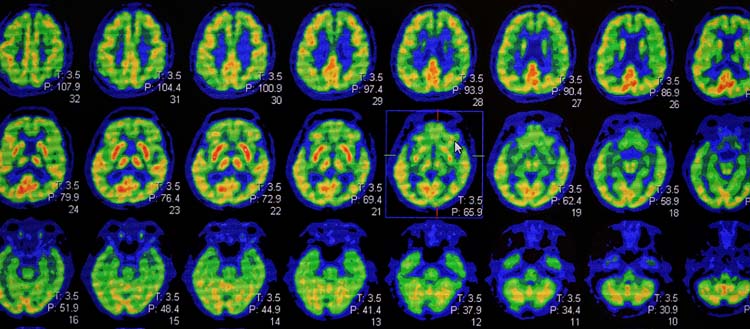

This diagnostic pathway has been developed on the basis of the scientific literature and from the practical experience of the specialists. After having examined the individual's complaints, performed memory tests and conducted a brain MRI, the specialist can now take advantage of these recommendations to classify the case into one of the eleven defined phenotypes, then look for biomarkers using the tests recommended by the international experts, namely lumbar puncture, amyloid PET, glucose PET, ioflupane SPECT, MIBG SPECT and tau PET.

[1] A diagnostic biomarker is a measurable biological characteristic linked to a disease. Biomarkers of neurodegenerative diseases are cerebral atrophy, cortical hypometabolism and the reduction of dopaminergic or adrenergic receptors. The specific biomarkers of Alzheimer's disease are amyloid and tau proteins. Tests that measure biomarkers are lumbar puncture, PET, MRI and SPECT.